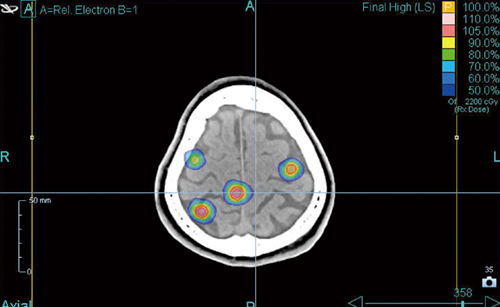

現在使用している治療計画装置「Accuray Precision」ならびに治療高速化オプション「VOLO」は,脳神経外科医師にも簡便に使っていただける内容である。アキュレイ社の講習を経た上で,導入直後から線量制約・線量処方なども併せて依頼している。特にGTV/臨床的標的体積(CTV)設定と線量分割に関しては,脳神経外科のポリシーが重要視される。転移性脳腫瘍の場合でも,患者の予後やQOLのバランスを取りつつ,適宜適切にSTIを行うためには,脳神経外科の視点は重要である。MLCに加えて,可変シリンドリカルコリメータ機能を持つIris collimator(IRIS)が選択可能なため,治療時間も短くなり,複数部位への対応も可能な点が脳神経外科に好評である(図2)。

図2 症例:多発転移性脳腫瘍

近在している腫瘍は同時に照射を行う。